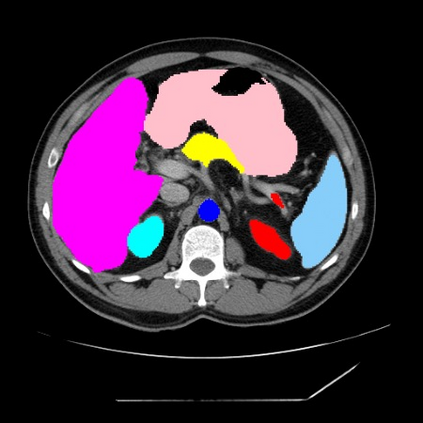

Integrating high-level semantically correlated contents and low-level anatomical features is of central importance in medical image segmentation. Towards this end, recent deep learning-based medical segmentation methods have shown great promise in better modeling such information. However, convolution operators for medical segmentation typically operate on regular grids, which inherently blur the high-frequency regions, i.e., boundary regions. In this work, we propose MORSE, a generic implicit neural rendering framework designed at an anatomical level to assist learning in medical image segmentation. Our method is motivated by the fact that implicit neural representation has been shown to be more effective in fitting complex signals and solving computer graphics problems than discrete grid-based representation. The core of our approach is to formulate medical image segmentation as a rendering problem in an end-to-end manner. Specifically, we continuously align the coarse segmentation prediction with the ambiguous coordinate-based point representations and aggregate these features to adaptively refine the boundary region. To parallelly optimize multi-scale pixel-level features, we leverage the idea from Mixture-of-Expert (MoE) to design and train our MORSE with a stochastic gating mechanism. Our experiments demonstrate that MORSE can work well with different medical segmentation backbones, consistently achieving competitive performance improvements in both 2D and 3D supervised medical segmentation methods. We also theoretically analyze the superiority of MORSE.

翻译:在医学图像分割中,整合高级语义相关的内容和低级解剖特征对于模拟这些信息非常重要。近期基于深度学习的医学分割方法已经显示出很有前景,可以更好地建模这些信息。然而,医学分割的卷积运算符通常在正则化网格上运作,这在本质上模糊了高频区域,即边界区域。我们在这项工作中提出了 MORSE,这是一个设计在解剖学水平上的通用隐式神经渲染框架,用于协助医学图像分割的学习。我们的方法的动机在于隐式神经表示已经被证明比离散化网格表示更有效地拟合复杂信号和解决计算机图形问题。我们方法的核心是将医学图像分割连续地对准粗糙的分割预测和模棱两可的基于坐标的点表示,并聚合这些特征来自适应地精细化边界区域。为了并行地优化多尺度像素级特征,我们借鉴了 Mixture-of-Expert (MoE) 的思想设计和训练我们的MORSE,使用随机门控机制。我们的实验表明MORSE可以很好地与不同的医学分割后骨干结合在一起,始终在2D和3D监督医学分割方法中实现了有竞争力的性能改进。我们还从理论上分析了MORSE的优越性。